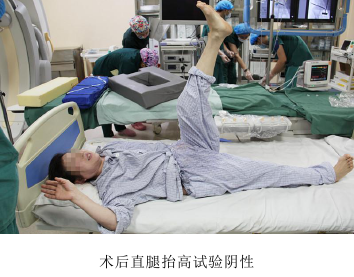

2017年3月17日,辽宁中医药大学附属医院骨伤二科,自主完成了院内首例治疗腰椎间盘突出症的椎间孔镜髓核摘除手术,开启了我院脊柱微创手术治疗的先河。此新技术的引进与开展,得到了院领导及医务处的大力支持,本次手术是由邓小磊医师在万贵良主任医师的协助下独立操作完成,受益者是一名患有腰5-骶1椎间盘突出症的57岁女性患者,此患者腰痛伴左下肢放射痛反复发作10年,复发10天,因疼痛无法下地活动行走,卧床10余天。术前经完善腰椎正侧位DR,腰椎CT和MRI等影像学检查,精准确定突出髓核的位置、性质及椎间孔骨质增生情况,详细规划手术策略,注重预判术中可能发生问题,提早制定解决方案。手术采取局部麻醉,切口约7mm,在DSA引导下,经椎间孔建立直径7mm的工作通道,使用椎间孔镜靶向摘除突岀的椎间盘髓核。手术医师在术中随时与患者语言交流,安全,顺畅。此例手术过程顺利,术后患者疼痛即刻缓解,并可下地行走。